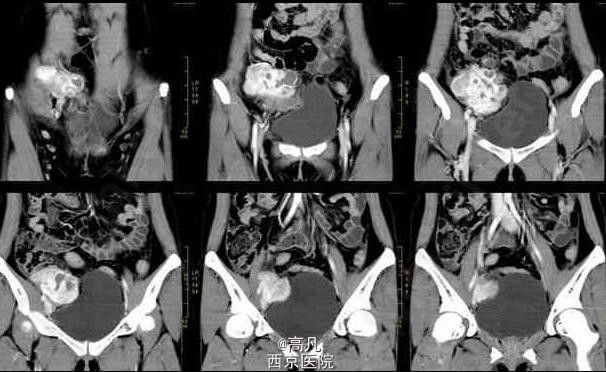

患者有周期性尿频、尿痛、血尿 辅查CT:右下腹可见囊实性不规则形肿块,实性为主。增强扫描不规则增厚的囊壁,内有多个大小不等囊变坏死区。